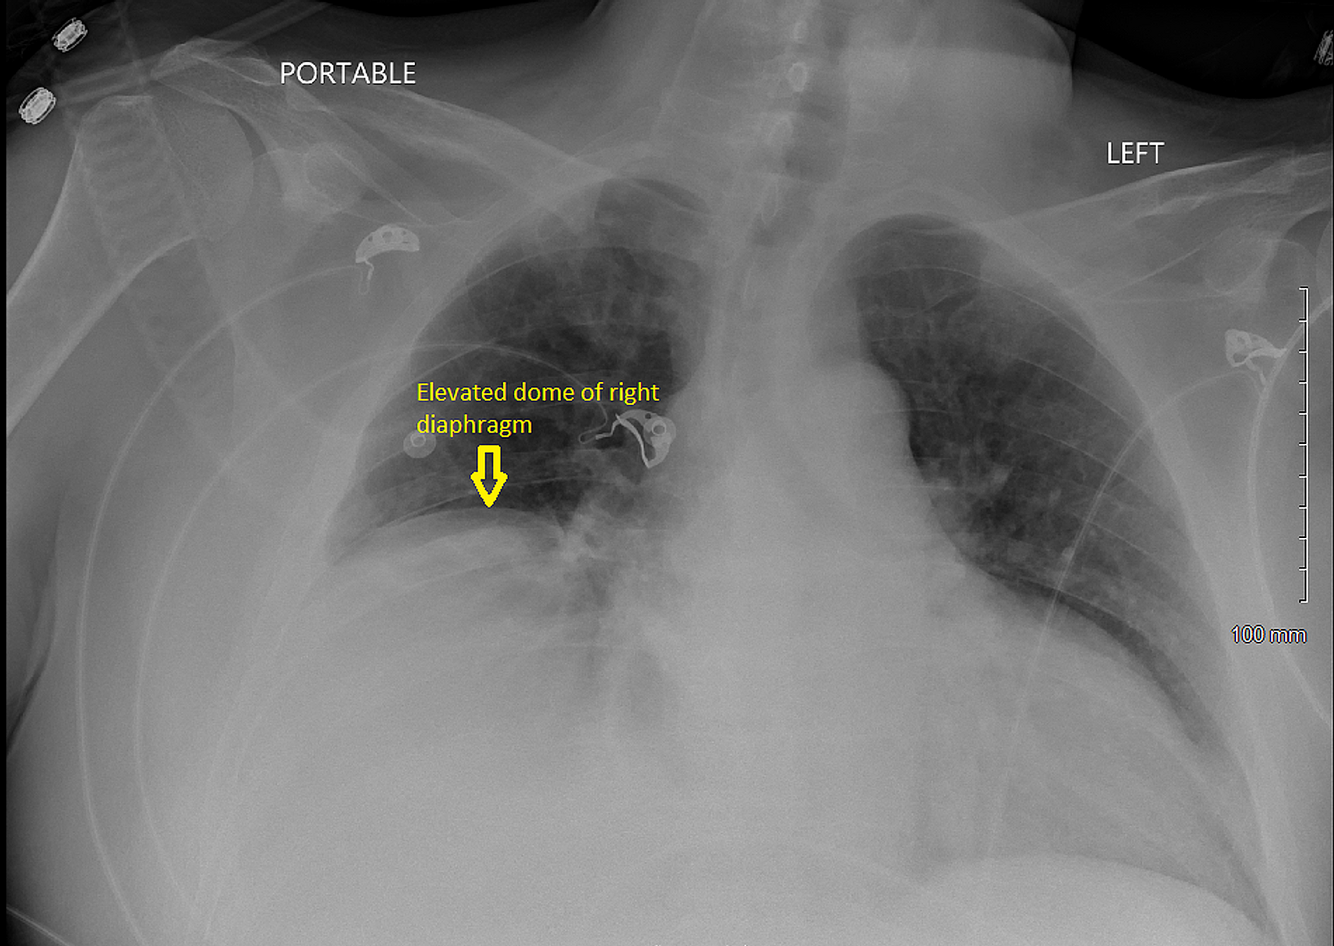

What Happens when the Phrenic nerve is Injured?

• Paralysis of the Hemidiaphragm

• Elevation of the Hemidiaphragm

• Paradoxical Movement of the Hemidiaphragm

Diaphragm Paralysis